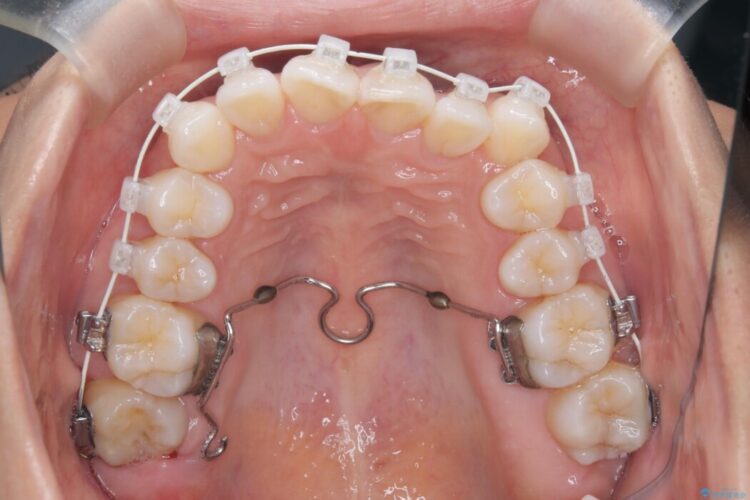

全体的にスペース不足ではありましたが、患者様は抜歯をしたくないとのご要望だったため、上顎の裏側に「トランスパラタルアーチ(TPA)」という装置を装着し、奥歯の幅を調整しながらスペースを確保する計画を立案。

トランスパラタルアーチを用いて右上7番目の歯を内側へ誘導し、正しい位置へと修正しました。

まずはこの装置で奥歯の土台を安定させつつ、ワイヤー装置による繊細な歯の移動を組み合わせることで、非抜歯で歯列全体のアーチを整えていきました。シザーズバイトが解消されたことで、奥歯でしっかりと物を噛めるようになり、顎の動きもスムーズに改善されました。